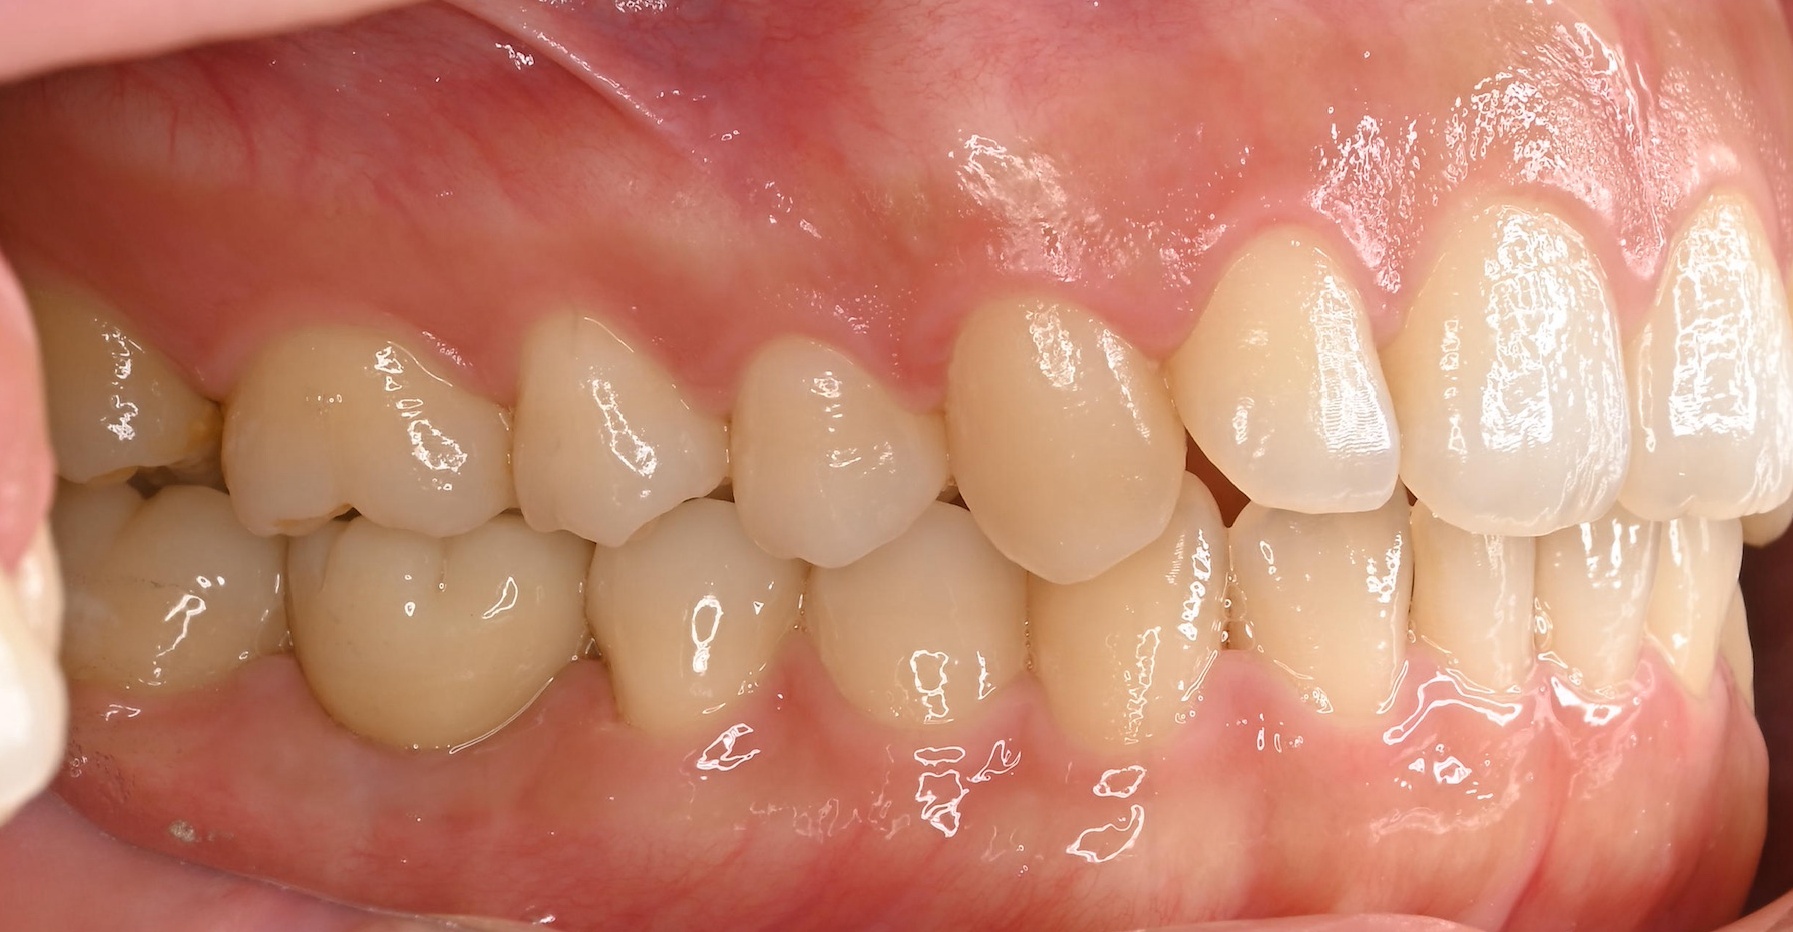

右下奥歯のインプラント症例

Before

• 右下6番欠損です。

• インプラントを埋入するのと同時にヒーリングキャップを取り付けました。

After

治療内容

右下の奥歯を根の先の膿が原因で抜歯された患者様です。

ブリッジ治療では両隣の歯を大きく削らないといけない為、インプラント治療を希望されました。

骨の治り方が歪で、頬側の骨が大きく足りないため骨造成を行い、インプラントを埋入した日にヒーリングキャップを装着し、インプラントが骨と結合するまで待ちます。

その後、型取りをし被せ物をスクリューにて装着しています。